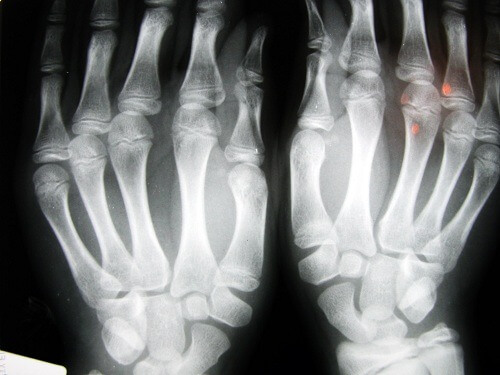

Many people ask if cracking their knuckles or popping their joints can develop into arthritis. If it is a regular, daily habit over the course of many years, then, in theory, the cartilage will be damaged.

One of the best known studies on this topic was made by Dr. Donald Unger. For 60 years he cracked the knuckles of the fingers on his left hand twice a day but did not do so on his right hand. Every year he examined his hands and never found traces of a degenerative disease, even in the hand that he “crunched”.

Another study examined 30 elderly people in a nursing home in Los Angeles. Those who had cracked their knuckles their whole life did not have osteoarthritis. In a third study, this time with adults 45 years old in Detroit, a different discovery was made. They found that the main problem was in the loss of strength in their grip. Over 80% of those studied also suffered from swelling in their hands.